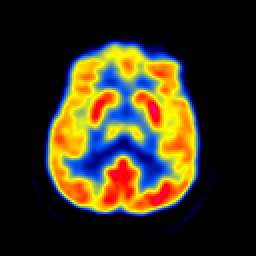

In image fusion, images obtained from different sensors are fused to generate a single image with enhanced information. In recent years, state-of-the-art methods have adopted Convolution Neural Networks (CNNs) to encode meaningful features for image fusion. Specifically, CNN-based methods perform image fusion by fusing local features. However, they do not consider long-range dependencies that are present in the image. Transformer-based models are designed to overcome this by modeling the long-range dependencies with the help of self-attention mechanism. This motivates us to propose a novel Image Fusion Transformer (IFT) where we develop a transformer-based multi-scale fusion strategy that attends to both local and long-range information (or global context). The proposed method follows a two-stage training approach. In the first stage, we train an auto-encoder to extract deep features at multiple scales. In the second stage, multi-scale features are fused using a Spatio-Transformer (ST) fusion strategy. The ST fusion blocks are comprised of a CNN and a transformer branch which capture local and long-range features, respectively. Extensive experiments on multiple benchmark datasets show that the proposed method performs better than many competitive fusion algorithms. Furthermore, we show the effectiveness of the proposed ST fusion strategy with an ablation analysis. The source code is available at: https://github.com/Vibashan/Image-Fusion-Transformer.